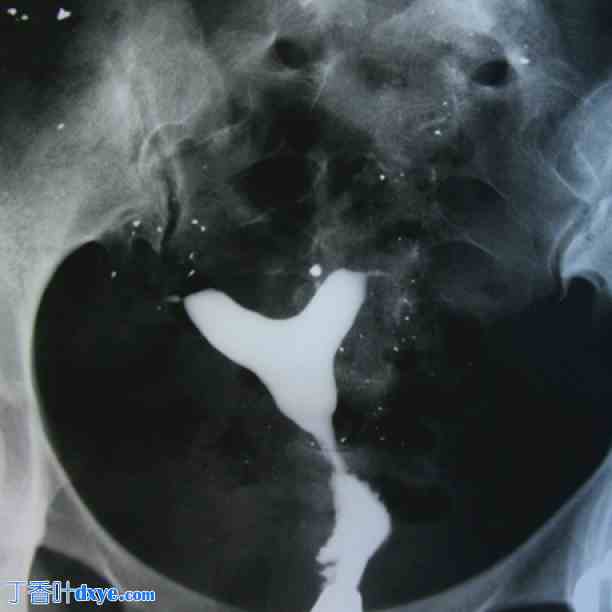

图 7。

正常宫腔。骨盆左侧及宫腔外聚集着细小的静脉石。静脉石在盆腔X光检查中很常见,但无临床价值。